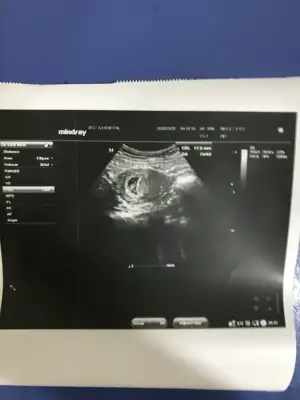

Ikra meyra İlk resim 6 haftalık ikinci resim 10 haftalık cinsiyet tahmini yapacak varmı kızlar

Eklentiler

Merhabalar birinci resimde 6 haftalık ikinci resimde 9+5 haftalık varmı cinsiyet tahmini yapıcam kızlar